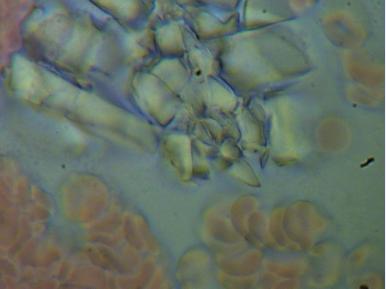

2.KRYSZTAŁY KWASÓW

Obecność kryształów soli kwasów w organizmie świadczy o jego zakwaszeniu. Sól może odkładać się w nerkach w postaci piasku lub kamieni , w stawach powodując stan zapalny i zwyrodnienia oraz w wielu innych narządach.

3.KRYSZTAŁY KWASU ORTOFOSFOROWEGO - którego obecność świadczy o zaburzeniu równowagi kwasowo-zasadowej. Wapń jest jednym z pierwiastków , które organizm wykorzystuje do przywrócenia tej równowagi . Jeżeli zakwaszenie jest duże powstają coraz większe kryształy , w konsekwencji mamy problemy z paznokciami, włosami , zębami oraz wzrasta zagrożenie osteoporozą.